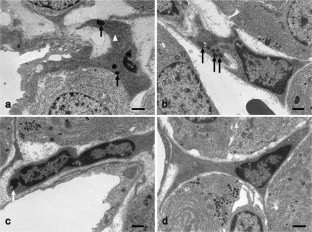

Prolactinomas are the most common tumor of the human pituitary. They result in excessive prolactin secretion and important changes in the vasculature. Pericytes are perivascular cells associated with capillaries and have crucial roles in physiological and pathological neovascularization. We previously reported that pericytes produce type I and III collagens in the anterior pituitary of adult rats. In addition, pituitary pericytes contained well-developed cell organelles and actively synthesized collagens during early postnatal development. However, the characteristics of pericytes in pituitary tumors are unclear. In this study, we used diethylstilbestrol (DES)-treated rats as an animal model of prolactinoma. Using five common pericyte markers, more pericytes were observed in rats treated with DES for 3 months (prolactinoma) compared to the control. Transmission electron microscopy revealed that attached and semidetached pericytes exhibited active cell organelles. Moreover, we identified pericyte migration between capillaries. Although the fine structure of pituitary pericytes was active in prolactinoma, expressions of type I and III collagen mRNAs were greatly diminished. In sum, the characteristics and functions of pericytes were altered in pituitary tumors. This study is the first to clarify fine structural changes of pericytes in rat prolactinomas and improves our understanding of the function of pericytes under pathological conditions.

Fig. 3